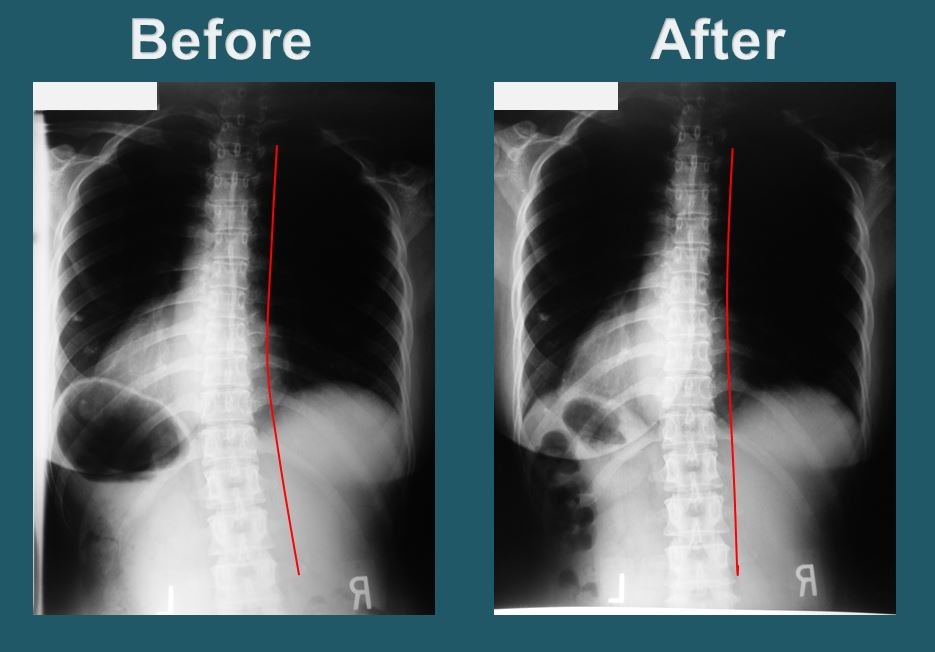

Dr. Park will take X-rays of the upper cervical region, neck, full spine, and pelvis to observe and examine the degree of misalignment. The doctor will then implement the procedure to restore head, neck and spinal alignment. This procedure is performed by the doctor’s own hands, without the use of any needles or electric therapy.

As soon as the vertebrae is aligned correctly, the brain will immediately start sending healing messages to those parts of the body affected by the misalignment and begin the natural self-healing process. Blockage of brain to body messages can be the direct or indirect cause of most health problems. On each visit, Dr. Park seeks to regain and maintain the proper alignment of the spine, aiding each patient through the process of recovery and healing.